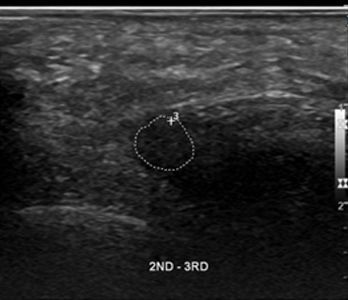

43세

남성 지간신경종

Before

2019.12.23

After

2020.03.18

50세

여성 지간신경종

2019.11.30

2020.02.14